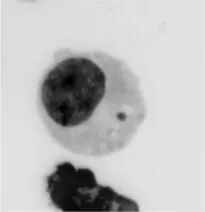

正因为这些科学家们不断研究CIN在癌症中的作用,癌症基因组学与细胞生物学之间的界限逐渐在消解。一方面,染色体所携带的遗传密码可以用复杂的基因组学手段破译;另一方面,染色体生命周期与细胞分裂过程中的分离行为基本上可以用分辨率较高的光学显微镜来跟踪。例如,分离过程中出现错误的染色体最终会出现在一个容纳小段DNA的“微核”(micro-nuclei)中,与细胞核——即“主核”——分离。微核一直被看作是区分癌细胞及周围正常组织的一个特征。多个研究组的工作显示,包裹微核的核膜经常破裂,把染色体洒到细胞质中,暴露在核酸酶下,同其它蛋白质一样被降解,变得四分五裂。

细胞分裂过程中,有许多染色体分离错误都可能导致微核形成。即使最终染色体并没有错误分离,也还是有可能形成微核。例如图2所示的情况,虽然染色体最终是平均分配给了两个子细胞,但由于分离滞后,左边的子细胞还是形成了微核。这些事件不互斥,也不独立,只是每一次发生都会加剧染色体的混乱。

在显微镜里苦寻良久,我们不仅观察到,发生CIN的细胞内,微核占了主体,还看到那些包含破裂微核的细胞带有一种与免疫相关的酶,叫做cGAS。cGAS于2013年首次被德克萨斯大学西南医学中心(University of Texas Southwestern)的James Chen(陈志坚)发现,它是一种定位于细胞质的双链DNA感受器。于是我们设想,微核破裂后,随之而来暴露在细胞质中的染色体可能会被癌细胞识别为危险信号,就像细胞识别出入侵的病原DNA那样。当然,随后我们便确认了,破裂的微核能够强有力地激活cGAS及其相关蛋白STING,进而激活固有免疫应答。但不像几天之内就能清除的急性病毒感染,癌细胞的细胞质中,微核破裂事件一起接着一起,导致炎症通路一直处于激活状态,炎症一直持续。